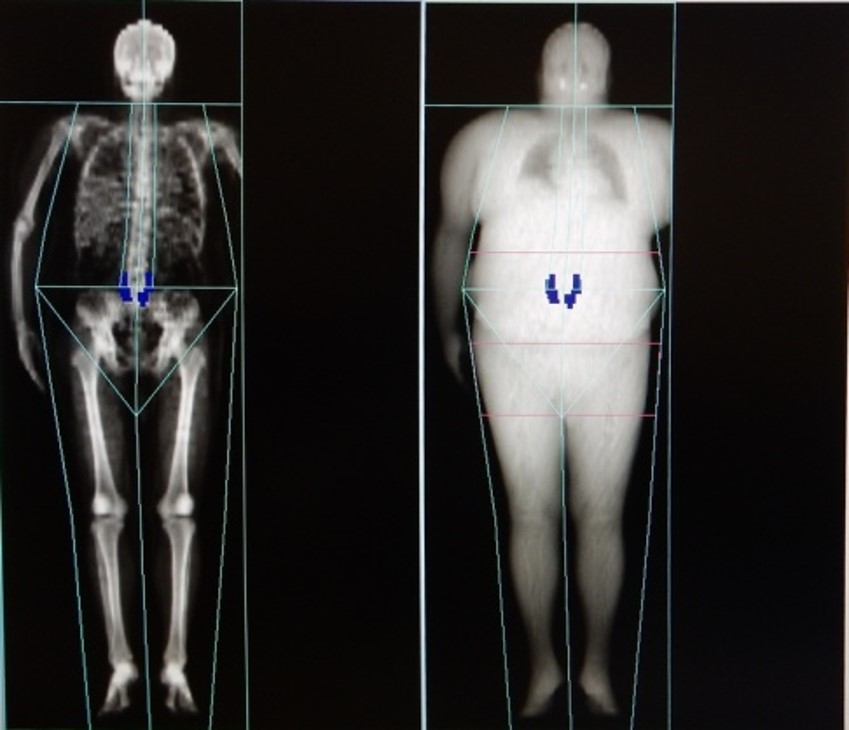

『全身骨』の検査の場合、旧装置では検査前に全身骨専用のQAファントムの撮影が必須で煩雑でしたが、本装置では通常の朝電源投入時のQAファントムの撮影で事足りるので、時間削減ができました。また、患者が極めて大柄で測定可能範囲に入らない場合は、右上肢は確実に含め左上肢を欠損させて撮影します。本装置では欠損部分を右上肢と同等と推測して左上肢の結果を算出することができるので、推測値ながら全身骨の骨密度を得られて便利だと思いました。